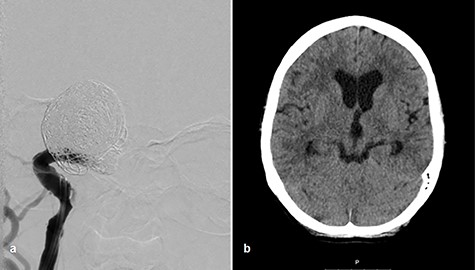

Afterward, we decided to perform aneurysm coiling and PAO. Prior to this, we repeated the occlusion test with clinical, angiographic and TCD control before and during induced arterial hypotension. In stand-by anesthesia with central venous catheter and invasive blood pressure monitoring, a 4-F catheter was placed in the left ICA and a 6-F guiding catheter was placed in the right ICA. Occlusion of the right ICA was performed with a balloon. With 100 mmHg mean blood pressure, we measured 78 m/s systolic flow in the TCD on the right MCA. The patient presented no neurological symptoms. Left ICA angiogram showed good crossflow perfusion of the right side over the anterior communicating artery. After a drop of mean blood pressure from 100 to 70 mmHg using intravenous administration of urapidil, there was no neurological deficit observed over the period of 30 min. Furthermore, there was no perfusion reduction and no delay of venous phase on the right side on the angiogram of left ICA (Fig. 2c and d), but we observed systolic flow reduction from 78 to 50 cm/s on the right MCA in the TCD during induced arterial hypotension. Based on the results of good collateral flow during occlusion test without neurological deterioration after hypotension challenge, we finally performed PAO by coiling with seven coils (Fig. 3a).

Coiling of giant aneurysm and parent vessel occlusion, p–a angiogram (a), CT scan on Day 1 (b).